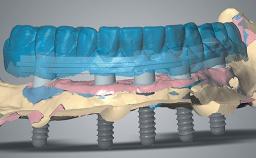

Rehabilitating an Edentulous Maxilla with Three Separate Bridges

A 55-year-old woman was referred to our clinic for implant therapy. She was healthy and had stopped smoking two years previously. Ten years before, the patient had received extensive dental treatment in both jaws. The patient reported that her dental condition had deteriorated progressively since that time. At the time of presentation, the maxillary bridge was loose. The clinical and radiographic examinations revealed a highly compromised situation for all the teeth that supported the bridge and for other teeth.

| # of Implants | 8 |

| Type of Implants | Reduced-Diameter|Two-Piece |

| Guided Surgery | Yes |

| Abutment Type | CAD/CAM |

| Prosthesis Type | FDP |